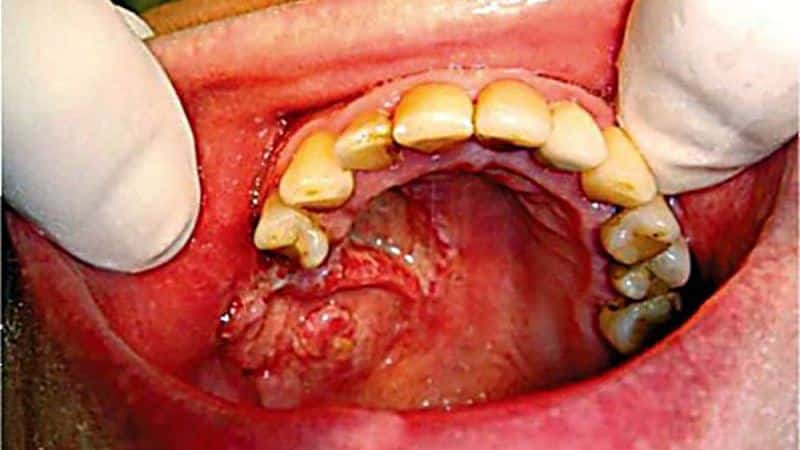

При подостром остеомиелите челюсти (фото выше) пациент может заметить свищи в воспаленной области, из которых выделяется гной или патологическая жидкость. С одной стороны, пациент может ощущать улучшение, но с другой — инфекция продолжает развиваться, что проявляется возникновением болевых ощущений через несколько дней.